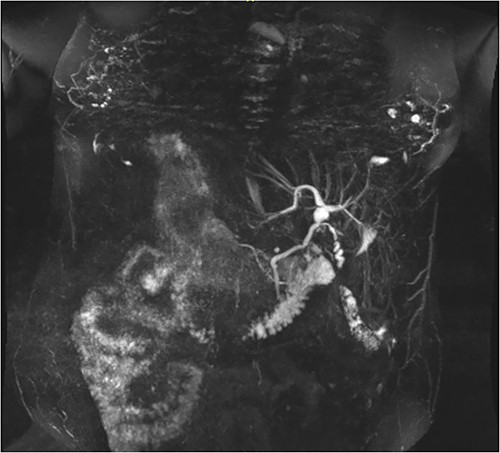

Following examination, a magnetic resonance cholangiopancreatography (MRCP) test was requested to exclude choledocholithiasis. 24 hours later, this confirmed gallstones, with 10 mm saccular dilatations near the hilar confluence (Figs 1 and 2). This dilatation was non-progressive according to previous scans, with unaffected pancreatic and intrahepatic ducts. Dilated portal vessels and varices were discovered to be directly communicating with the gallbladder fossa, suggestive of portal venous communication.

Coronal MRCP scan demonstrating a 10 mm area of saccular duct dilatation at the hilar confluence. Large, dilated vessels/varices surrounding the gallbladder fossa can also be appreciated.

Follow-up with a congenital cardiac consultant confirmed that there would be no major cardiac risks associated with cholecystectomy. However, the main risk identified by abdominal CT scans was the tortuous recanalized portal vein circumscribing the gallbladder and providing main portal inflow to the liver, presenting a high risk of bleeding, portal venous thrombosis, or worsened portal hypertension. Given the risks of surgery and minimal symptoms, the patient opted for a ‘watch and wait’ approach.